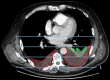

Methods: Multicentre retrospective cohort study. Caudal sections of the thorax derived from abdominal contrast enhanced computed tomography (CECT) performed in the early phase of AP were assessed. Independent predictors of severe AP were identified by binary logistic regression analysis. A one-year survival analysis using Kaplan-Meier curves and log rank test was performed.

Results: 358 patients were analysed, finding pleuropulmonary pathologies in 81%. CECTs were performed with a median of 2 days (IQR 1-3) after admission. Multivariable analysis identified moderate to severe or bilateral pleural effusions (PEs) (OR = 4.16, 95%CI 2.05-8.45, p<0.001) and pre-existing CLD (OR = 2.93, 95%CI 1.17-7.32, p = 0.022) as independent predictors of severe AP. Log rank test showed a significantly worse one-year survival in patients with bilateral compared to unilateral PEs in a subgroup.